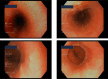

Case presentation: Here, we present a rare case of lymphocytic esophagitis in a patient with multiple allergies and suspected eosinophilic esophagitis. A 28-year-old woman with polyvalent sensitization to food and inhalant allergens presented with intermittent dysphagia, a sensation of a foreign body in the throat, itchiness of the oral cavity after ingesting certain foods, heartburn, and prolonged chewing time. A skin prick test showed positive results for birch-tree, alder, hazel, and rye pollen, as well as house dust mites. Apart from obesity (BMI 30 kg/m2), multiple pustules and excoriations on the skin, her physical examination was insignificant. Esophagogastroduodenoscopy (EGD) was performed revealing full-length but discrete trachealization of the esophagus. A barium swallow test showed slowing of esophageal peristalsis in the recumbent position. No esophageal pathology was observed. A histopathological analysis of mucosal samples revealed slight hyperplasia of the basal layer of the esophagus, and the stomach showed changes typical of chronic gastritis.